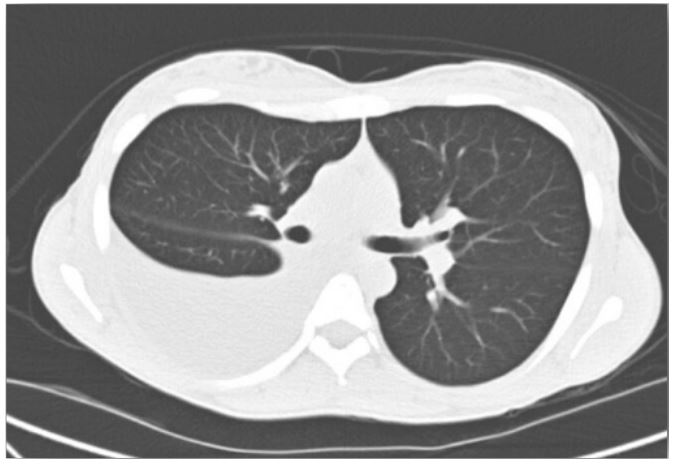

Figure 1: Computed tomography chest revealed a large right-sided pleural effusion.

On admission, her vitals were within normal limits. Physical exam revealed an ill-appearing female who appeared in mild discomfort with significantly diminished lung sounds over the right lower chest and dullness to percussion. Her abdomen was non-tender but was moderately distended with a positive fluid wave and shifting dullness. Other systems were unremarkable. Initial lab values showed microcytic anemia with Hgb of 7.6, but normal renal and hepatic function testing. Chest, Abdomen and Pelvis CT without contrast showed a moderate right hydropneumothorax, moderate to large pleural effusion without lung mass, as well as large ascites and heterogeneous uterus with questionable prominent cervix, and normal ovaries.